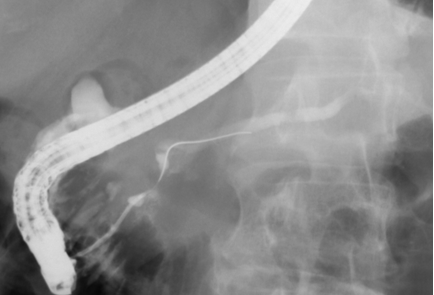

첫째는 특수 제작된 내시경(십이지장경)을 식도, 위를 거쳐서 십이지장 제 2부까지 유치시키고, 췌-담관이 십이지장으로 개구되는 유두부를 찾아서 육안으로 관찰하고, 카테터(가느다란 관)를 내시경 내의 작업관을 통해 췌관 혹은 담관으로 삽관한다.

둘째는 삽관된 카테터로 방사선 조영제를 주입하여 담관 또는 췌관에 대해 방사선 투시 및 촬영을 하여 진단을 하고 필요하면 유두부를 절개하여 담관-췌관의 병을 치료하는 것이다. 이런 시술을 내시경 역행성 담도-췌관 조영술(ERCP)이라고 한다. 즉, 이 검사는 내시경 검사와 방사선 검사 둘 다를 포함한다. 따라서 ERCP를 시술하는 의사는 내시경 술기와 투시 조영술 모두에 전문가이어야 한다. 또한 ERCP를 이용한 중재적 시술은 상부소화관내시경 검사보다 시간이 더 걸리고 중증의 합병증 위험이 있어서 모든 내시경의사가 ERCP를 할 수는 없고 전문적인 수련 과정을 이수한 후에 시술을 하는 것이 바람직하다.